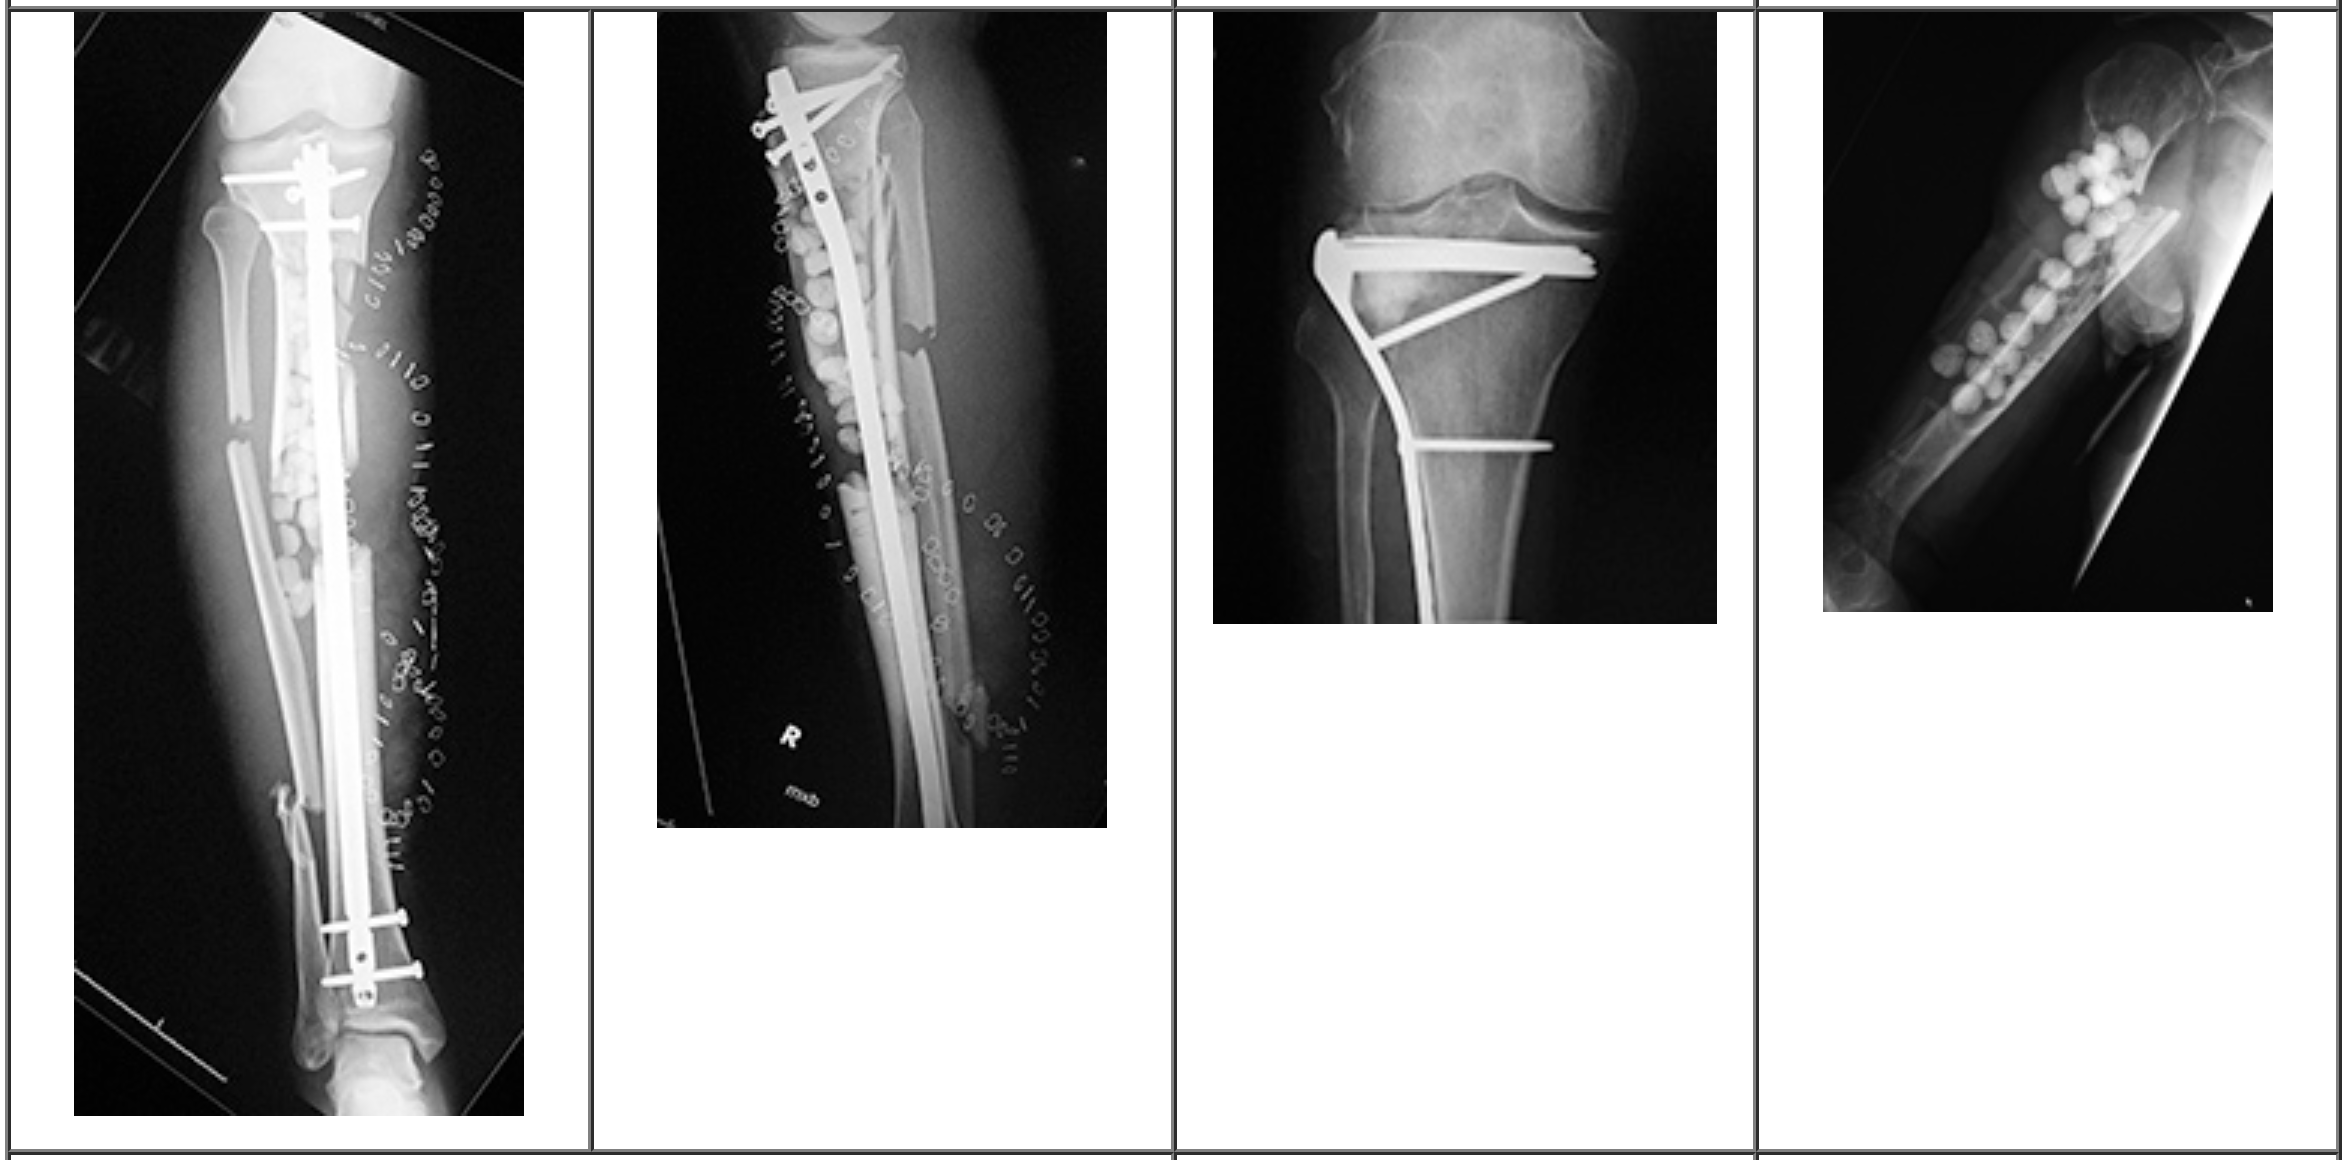

创伤骨科的“急救包”

在严重车祸或高处坠落导致的粉碎性骨折中,常伴有骨质缺损。

例如在胫骨平台骨折或跟骨骨折中,关节面的塌陷需要植骨支撑。此时,库存的股骨头可以随时取用,无需额外增加手术时间去取自体骨,对于缩短危重患者的手术时间、减少出血量具有至关重要的意义。

脊柱融合术的“桥梁”搭建

脊柱侧弯矫形、腰椎滑脱或椎管狭窄手术中,脊柱融合是治疗的关键。

医生将处理后的股骨头修剪成适合椎间隙大小的骨块,或者将其粉碎后填充在椎间融合器(Cage)内。